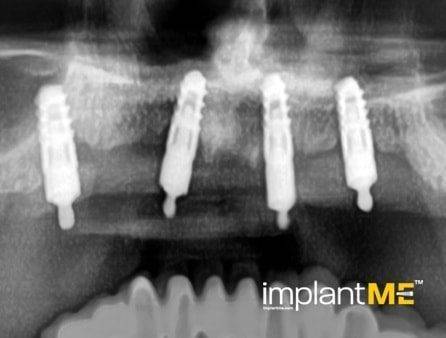

Τα ελκυστικά και ιδιαίτερα υγιή δόντια δεν είναι μόνο καθοριστικό μέρος της εμφάνισής μας, αλλά και της προσωπικότητάς μας. Παλαιότερα, η απώλεια ενός ή περισσοτέρων δοντιών είχε καθοριστικό αντίκτυπο στον τρόπο εμφάνισης των ανθρώπων. Λόγω της σύγχρονης στοματικής εμφυτευματολογίας, αυτό δεν συμβαίνει πλέον. Με συγκριτικά μικρές χειρουργικές επεμβάσεις από το στόμα, μεμονωμένα ή όλα τα ελλείποντα δόντια μπορούν να αντικατασταθούν από εμφυτεύματα, αισθητικά και λειτουργικά ίσα με τα φυσικά δόντια. Μέσω της εισαγωγής εμφυτευμάτων που σχηματίζονται σε ρίζα, είναι δυνατόν να αποφευχθούν αλλοιώσεις των γειτονικών δοντιών και να αγκυρωθούν στεφάνες που δύσκολα διακρίνονται από τα πραγματικά δόντια στα κενά των δοντιών. Οι στεφάνες ή οι γέφυρες που υποστηρίζονται από εμφύτευμα στερεώνονται στα εμφυτεύματα που είναι αγκυροβολημένα στο οστό, γεγονός που δίνει στους ασθενείς μια αίσθηση μάσησης σχεδόν διακριτή από τα δόντια τους. Σε περίπτωση πλήρους έλλειψης δοντιών, τα εμφυτεύματα μπορούν να παρέχουν αξιόπιστες αγκυρώσεις για αφαιρούμενα προσθετικά καθώς και για μεγάλες σταθερές γέφυρες.

Τα οδοντικά προσθετικά που υποστηρίζονται από εμφύτευμα βρίσκονται όσο πιο κοντά μπορείτε να φτάσετε στα φυσικά δόντια. Τα στεφάνια των εμφυτευμάτων βαθμολογούνται με τη φυσική τους εμφάνιση, τα εμφυτεύματα με τη σταθερότητα τους και και τα δύο με τη θετική τους επίδραση στη λειτουργική συντήρηση ολόκληρης της μαστιχικής συσκευής.